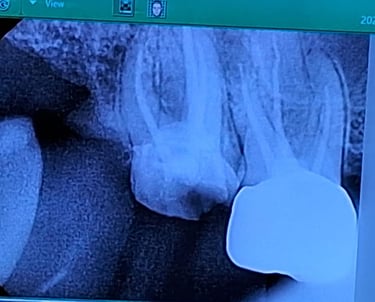

Root Canal Dentistry

Root canal treatment removes infected pulp from inside the tooth, cleans and seals the area to prevent reinfection, and helps save the natural tooth.